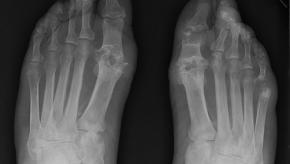

Gout Flare and Treatment Studies Lacking in Severe Chronic Kidney Disease

Gout is a common comorbidity amongst those with chronic kidney disease (CKD), with the added challenge of choosing best therapies in the setting of declining renal function. A systematic literature review notes significant deficiencies regarding the efficacy and safety outcom

Read ArticleStarting Febuxostat During an Acute Gout Flare

A randomized controlled trial in gout patients has shown that starting febuxostat during an acute gout flare was without ill-effects and did not prolong the gouty attack.